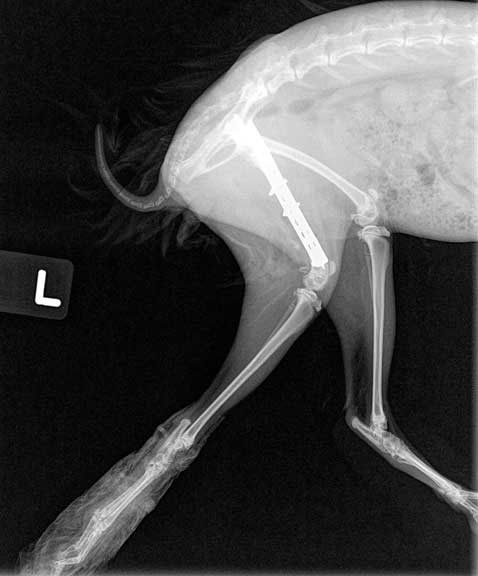

Can you visualize the 3 screws and 2 cerclage wires over the bone plate in this post operative VD (venture-dorsal) radiograph of the pelvis?

This is the lateral view of the plate